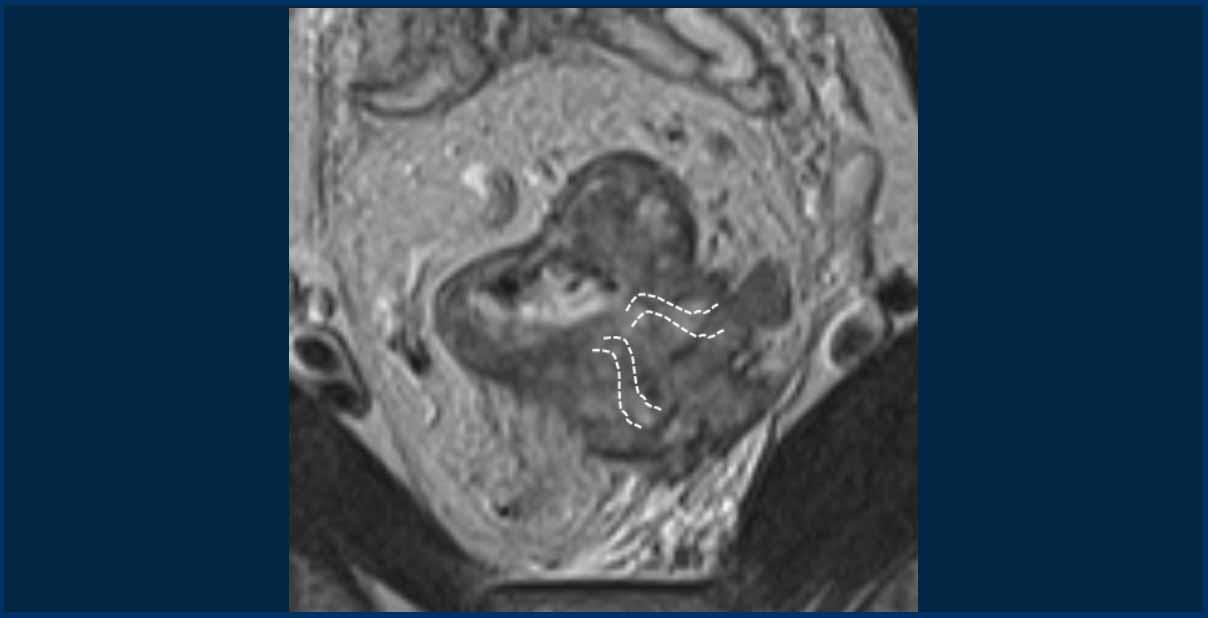

EMVI được nghi ngờ nếu chúng ta thấy tín hiệu khối u lan vào mạch máu lân cận, khi mạch máu bị giãn rộng bởi khối u, hoặc nếu khối u phá vỡ ranh giới mạch máu (hình minh họa).

Ví dụ

I need the HTML text fragment to translate. It seems like the message got cut off – you only provided “This image demonstrates” without the full text or HTML content.

Could you please share the complete HTML text fragment you’d like me to translate to Vietnamese?Bệnh EMVI+, cho thấy tín hiệu khối u lan vào mạch máu lân cận, dẫn đến giãn nở mạch máu và phá vỡ đường viền.

Cạm bẫy: Đánh giá EMVI trong các khối u có sự phát triển ngoài thành đại trà

Trong quy mô lớnKhối u T3cd-4với sự mở rộng ngoài thành ruột lan rộng vào mỡ quanh trực tràng, một cách tiếp cận thực tế là phân loại chúng làEMVI+.

Trong ví dụ được hiển thị, khối u xâm lấn vào lớp mỡ quanh trực tràng từ vị trí 3 đến 5 giờ, xóa mờ lớp mỡ mạc treo trực tràng ở vùng này.

Mặc dù sự xâm lấn của từng mạch máu riêng lẻ có thể không thể phân biệt được, nhưng có thể giả định một cách hợp lý rằng các mạch máu trong khu vực này đã bị khối u xâm lấn hoàn toàn.

Các đường đứt nét chỉ vị trí tiềm năng của các mạch máu.